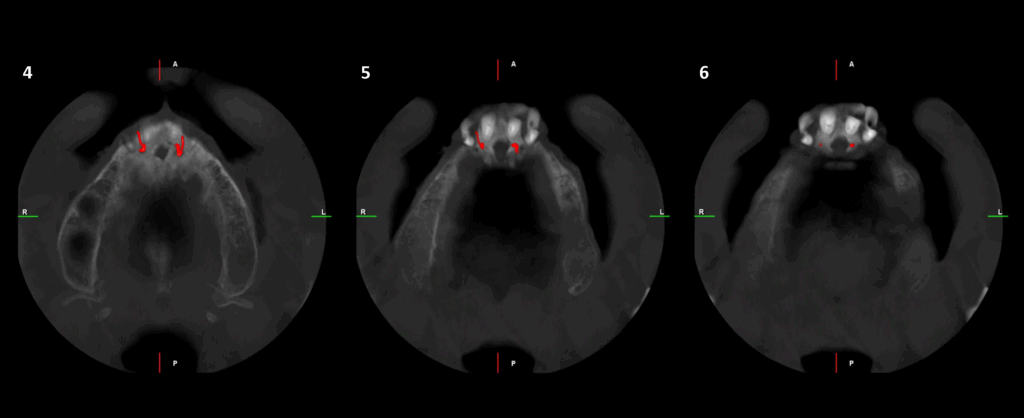

CORTES AXIALES

En el estudio complementario mediante tomografía computarizada de haz cónico (TCHC), se identifica la presencia del canalis sinuosus en el maxilar derecho, con trayecto que se dirige hacia la región ósea palatina correspondiente a las piezas 12 y 11. Asimismo, se evidencia un canalis sinuosus en el maxilar izquierdo, que se origina en la pared lateral de la fosa nasal izquierda y se dirige hacia la región ósea palatina y apical de las piezas 21 y 22.

Adicionalmente, se observa fractura radicular en la pieza 12, asociada a una imagen osteolítica periapical. Se identifican también fracturas radiculares con desplazamiento en las piezas 21 y 22. En la región correspondiente a la pieza 23, se evidencia un fragmento dentario sobre la cortical ósea vestibular.